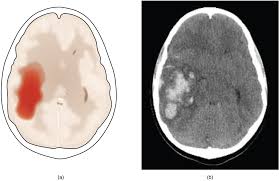

Xuất huyết/ chảy máu

Xuất huyết trong não (nhu mô)

- Nguyên nhân: Phình mạch Charcot-Bouchard, Tăng huyết áp, Tự phát

- Xảy ra ở hạch nền, đồi thị, cầu não, tiểu não